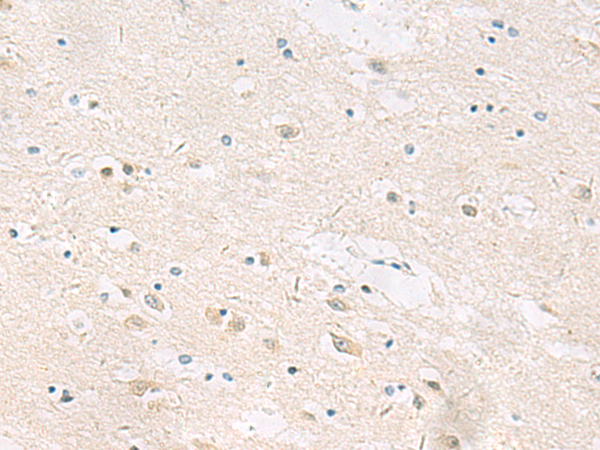

分类: 科研抗体货号: P03266别名: CIP; CINAP; AD-004; hCINAP; CGI-137应用: IHC反应种属: Human, Mouse, Rat